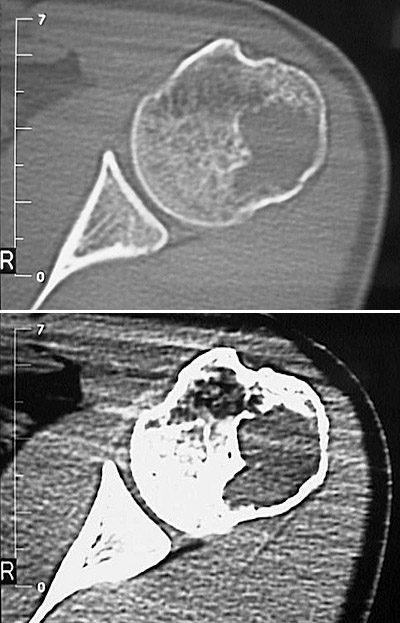

The CT scan views above demonstrate a large lytic area in the proximal humerus as a result of growth of an osteosarcoma. The pathologic loss of normal bone cortex resulted in a pathologic fracture.